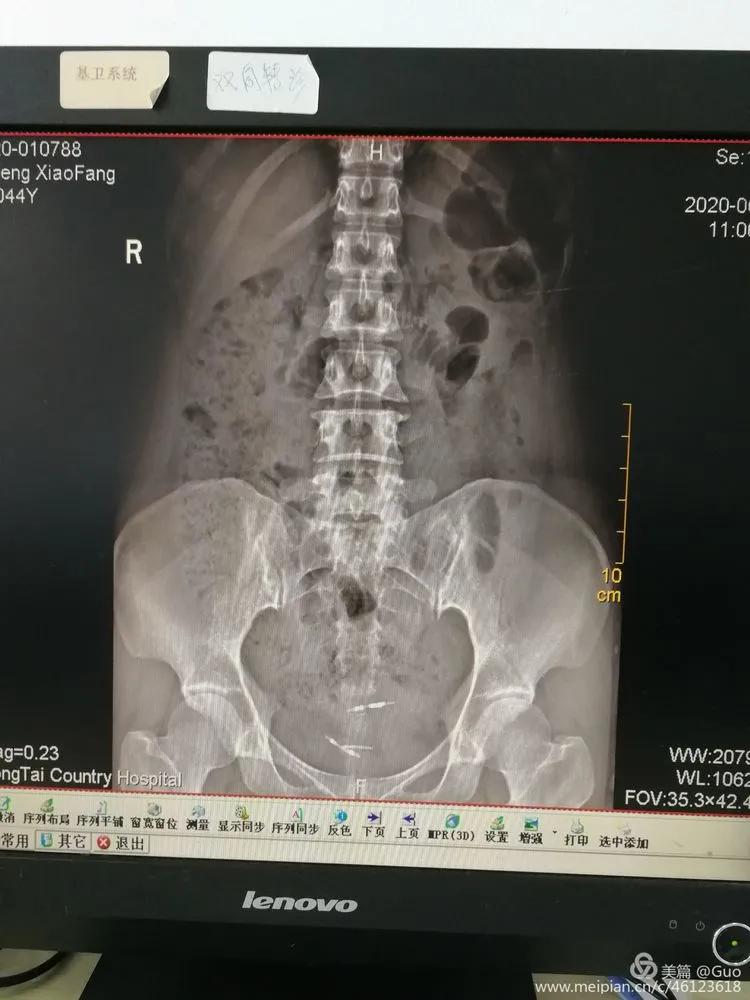

2020年6月17日,我院外科由范晓健主任及郭以滨副主任医师成功为一个43岁女性患者从膀胱内取出“异位”的节育环。13年前,患者置入第一个节育环。8年前,因意外怀孕发现第一个节育环“消失了”,于是置入第二个节育环。2年前,患者反复出现排尿后疼痛,自行服用“消炎药”症状可缓解。近来,排尿后疼痛加剧就诊外院考虑膀胱内高密度影,考虑膀胱结石可能。6月16日就诊我科行泌尿系CT及KUB检查确认膀胱内是“异位”的节育环。完善术前检查及准备后,今早在肾镜下见节育环表面附有结石,碎石后将节育环顺利取出,用微创的方法为病人解除了病痛。术前KUB示两个节育环

术前CT